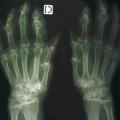

Chondrocalcinose articulaire

ARTHROPATHIES A CRISTAUX

Image